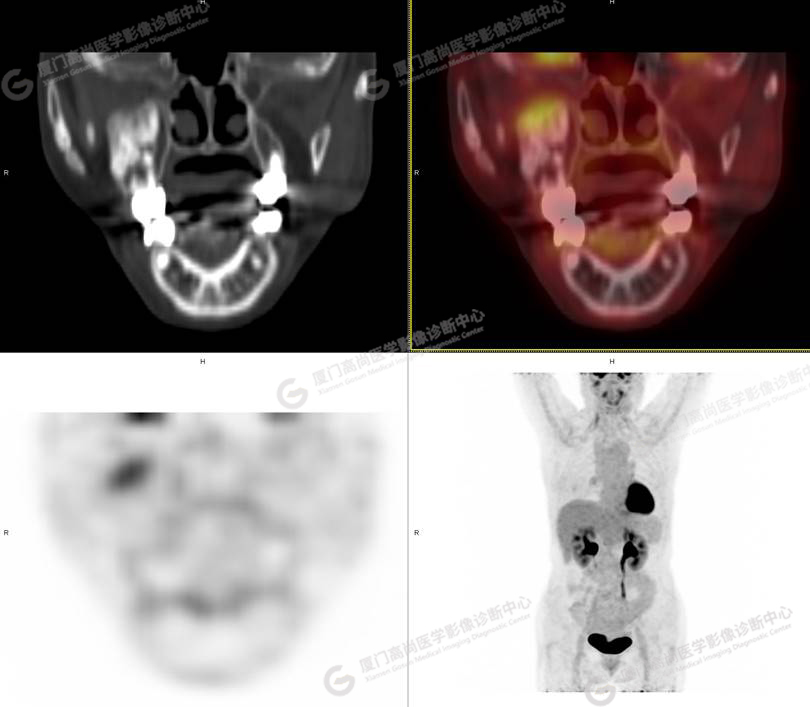

圖1

圖3

PET/CT所見:右側(cè)上頜骨、右側(cè)顴骨及右側(cè)額骨骨質(zhì)膨脹,其內(nèi)密度不均勻性增高,部分放射性攝取輕微增高,SUVmax 2.27。